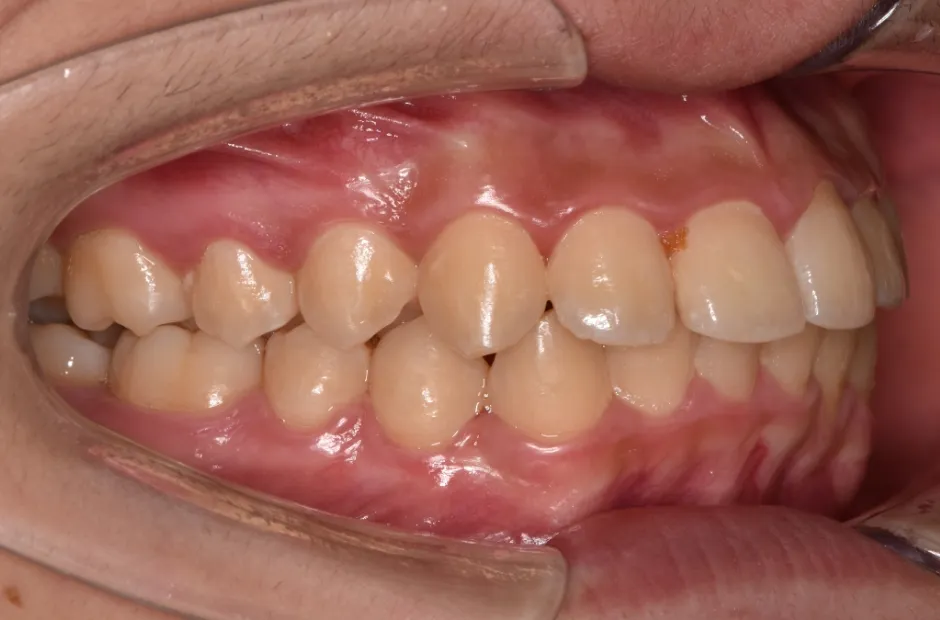

ブラケット矯正

前歯部反対咬合

| 診断名・主訴 | 前歯部反対咬合 |

|---|---|

| 年齢・性別 | 14歳・男性 |

| 治療期間・回数 | 1年2か月 |

| 治療に用いた主な装置 | ブラケット矯正 |

| 抜歯部位 | なし |

| 治療費 | 60万円(税抜) |

| リスク・副作用 | 装置による違和感・疼痛・歯肉退縮・歯根吸収・虫歯のリスクなど |

治療後